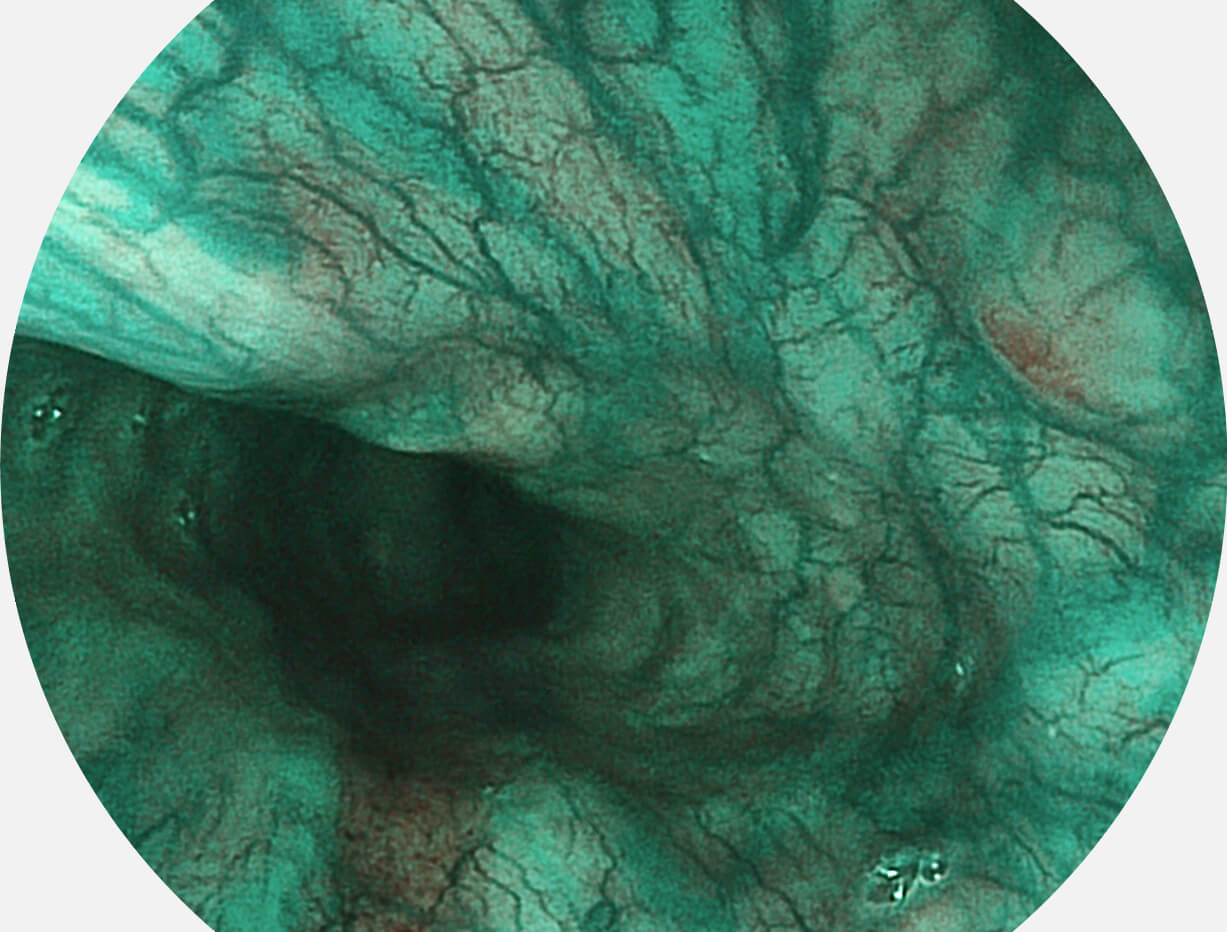

Versatile Intelligent Staining Technology, VIST

强调浅层黏膜结构的同时,保证照明亮度和提升浅层微血管与中层血管颜色对比度,病变边界更清晰。

白光图像

VIST图像

采用光路合束技术,光谱自由度高,实现了更丰富的照明模式,染色模式SFI及VIST,从远景到近景,助力消化道早期疾病诊断。